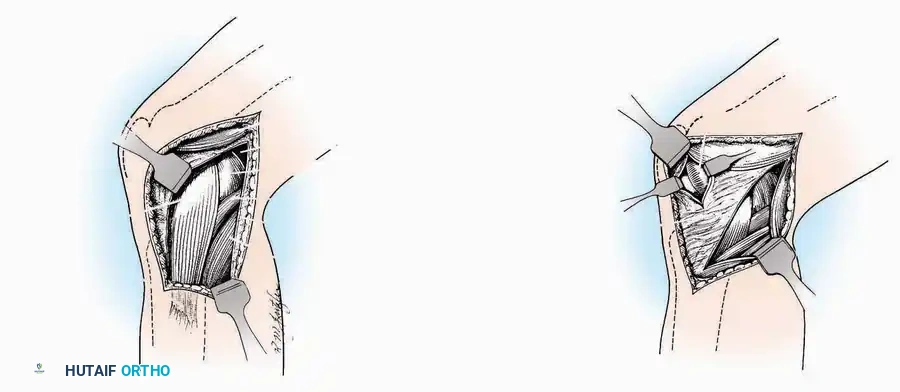

Dorsomedial Approach

Indications: Preferred approach for primary and revision first MTP arthroplasty, arthrodesis, and complex bunion corrections due to superior angiosome preservation.

Surgical Technique:

* Incision: Begin just proximal to the IP joint and extend proximally for 5 cm, running parallel and strictly medial to the EHL tendon.

* Exposure: Divide the superficial fascia. Identify and retract the EHL tendon laterally.

* Capsulotomy: The capsule can be incised longitudinally in the exact plane of the skin incision, allowing for subperiosteal elevation of the capsule medially and laterally, preserving the vascular supply to the medial skin flap.